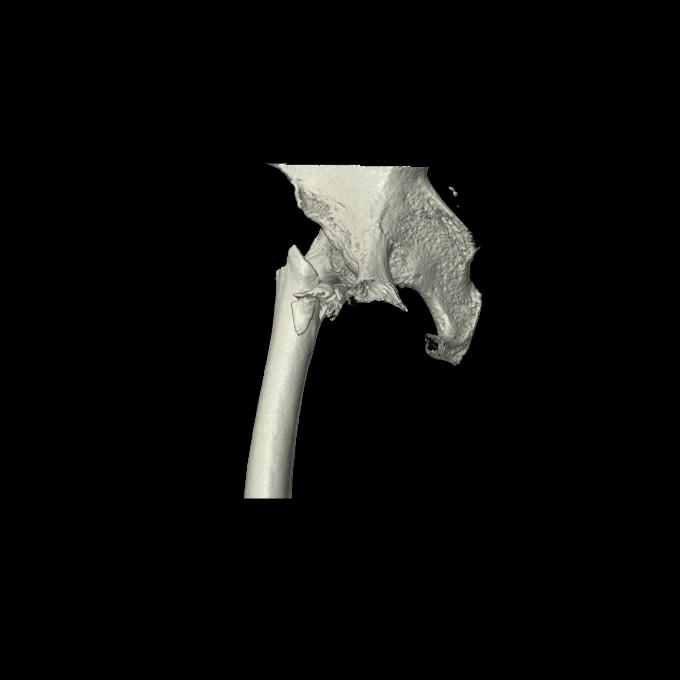

110286 2/17 股関節 2R 74歳女性 右人工骨頭

82084 1/14 1/20 股関節 2R 78歳男性 右人工骨頭